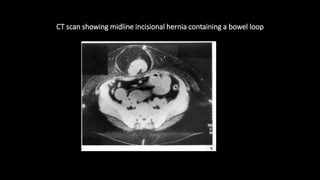

CT scan showing midline incisional hernia containing a bowel loop

 CT findings

• Free fluid collection within hernia sac

• Bowel wall thickening

• Abnormal bowel wall enhancement(hypo or hyper attenuating)

• Proximal bowel dilatation

• Herniated bowel segment and involved mesentery are shorter in length

CT scan showingmidline incisional hernia containing a bowel loop